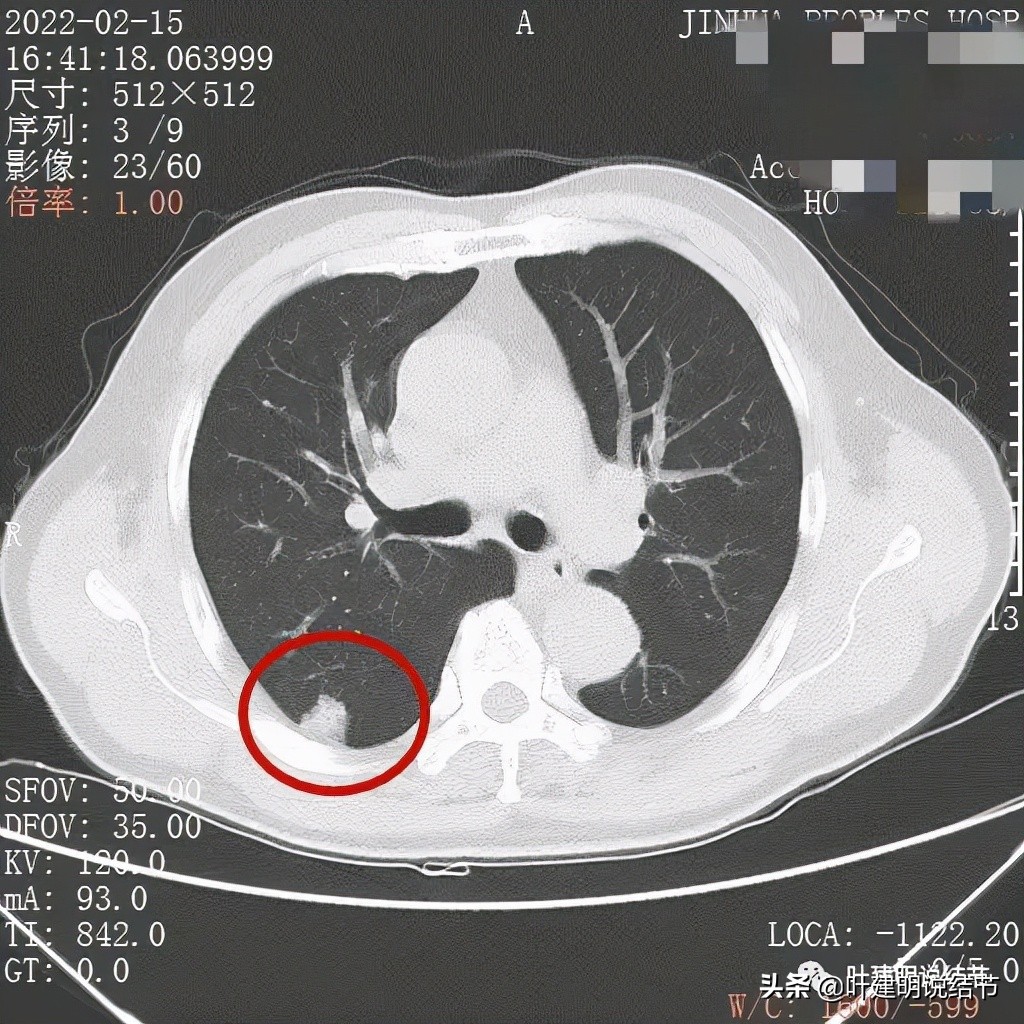

我们先来看下他的CT平扫5毫米层厚的图像:

病灶基本实性,但边缘稍不平整,有的边比较平直,但仍是不光滑的

病灶的部分边缘呈锯齿状,不平整,更谈不上光滑